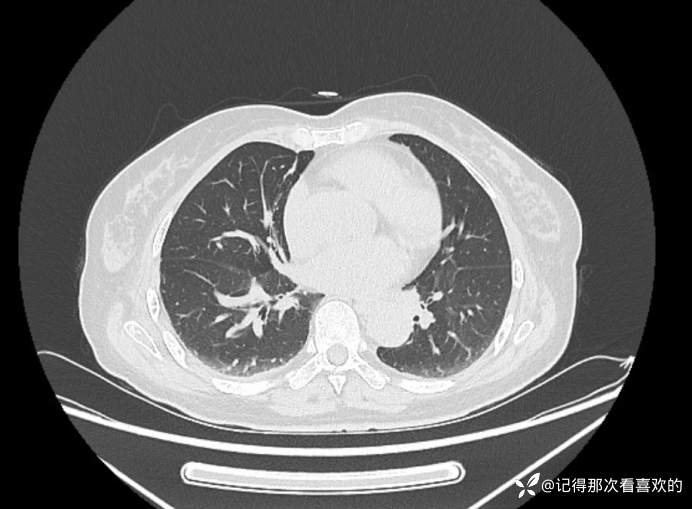

转科后查:2025-07-09血常规:*白细胞计数4.30×10^9/L,*血红蛋白120g/L,*血小板计数75×10^9/L↓;2025-07-11 铁蛋白 753.50ng/ml↑;血沉 12.00mm/h;降钙素原 0.21ng/ml,白介素6 329.0pg/mL↑;2025-07-12 血常规:*白细胞计数 4.99×10^9/L,中性粒细胞百分数78.9%↑,淋巴细胞计数 0.80×10^9/L↓,*血红蛋白115g/L,*血小板计数42×10^9/L↓;降钙素原1.21ng/ml,C反应蛋白35.50mg/L↑,白介素6 22.4pg/mL↑;血沉 14.00mm/h;甲型/乙型流感病毒抗原检测(呼吸道病毒抗原检测)、抗中性粒细胞胞浆抗体5项测定(ANCA)、登革热病毒检测(抗原+抗体)、新冠病毒核酸单人单检、粪便隐血试验(OB):阴性。免疫球蛋白G4(IgG4)、血液疟原虫检查、异常凝血酶原(PIVKA-Ⅱ)测定、粪便常规:未见明显异常。2025-07-11床边心电图:窦性心律,左心室高电压,ST-T异常。